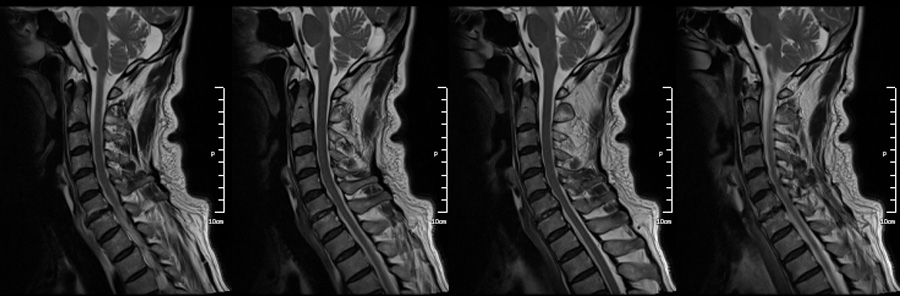

[ֹȣ : 20100311200600oo5374] 169 72 64 ̾ ȱֺ̾ǰ ̸ MRI߽ϴ. Ͻð ȣִ ƮĪ ȮϿ ͵帮. : ̴ Ʈ ؼ ڸ ϴ Ͻø ƮĪ ϸ鼭 ٰ մϴ. 2010-04-07 17:54:53 ----------------- Ұ ۼϽ ------------------------ ֽϴ. ȿ ߺ ֽϴ no 4846 date 2010-04-11 18:44:06 hits 20 name ± (hao2024@hanmail.net) IP: 122.32.41.55 63 Ǵ ±Դϴ. ó ãҴµ ˰ ũϴ. ʹ ýϴ. ߿ ǥغԸ ˰ԵǾ ó ִ° ֽϴ. ̰ ô Բ ʵ ģϰ ֽð ڼϰ ƮĪ ּż ҽϴ. ¿߿ ϰ ּż 帳ϴ. е Ͻð ̿ϼż ȣDZ ٶϴ. |